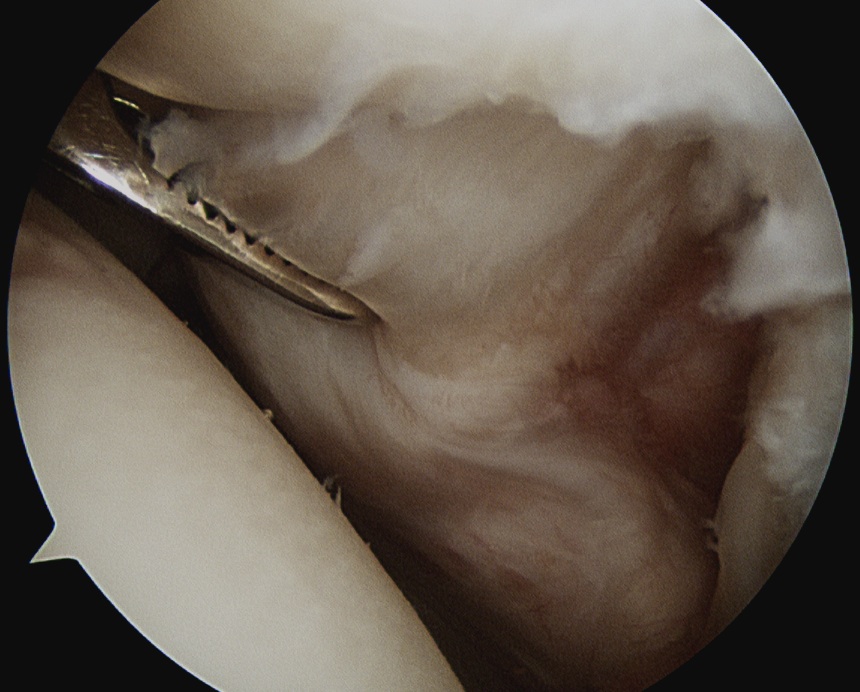

Medially dislocated biceps tendon with upper border subscapularis tear

Full thickness tear of subscapularis off insertion revealed with grasper